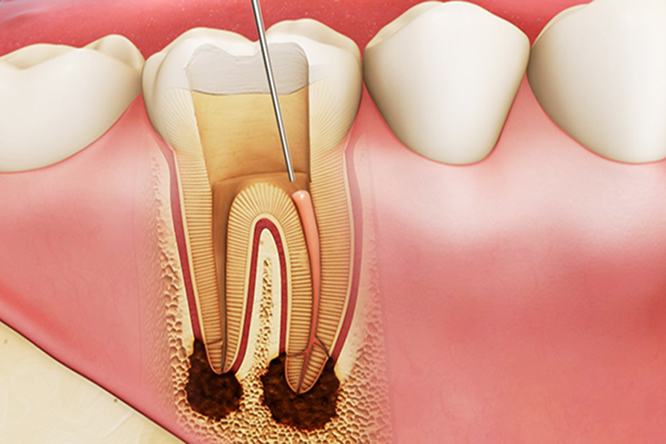

Trong cấu trúc răng, tủy răng đóng vai trò rất quan trọng là cung cấp dinh dưỡng nuôi sống và giúp răng luôn vững chắc, và khi tủy răng bị viêm nếu không được điều trị tủy răng kịp thời gây ra nhiều hậu quả nghiêm trọng đối với sức khỏe của bạn.

Khi các bước chuẩn bị đã hoàn tất, bác sĩ tiến hành điều trị tủy răng, sử dụng mũi khoan mở đường vào buồng tuỷ vừa đủ rộng để thao tác lấy tủy được diễn ra thuận lợi và dễ dàng trám bít phục hình. Tiếp đến bác sĩ sử dụng dụng cụ chuyên dụng để lấy sạch tuỷ răng, vi khuẩn rồi tạo hình ống tuỷ bơm rửa nhiều lần làm sạch hoàn toàn khoang tủy. Sau đó tiến hành chụp phim x-quang kiểm tra tủy viêm có còn đọng lại trong ống tủy không.